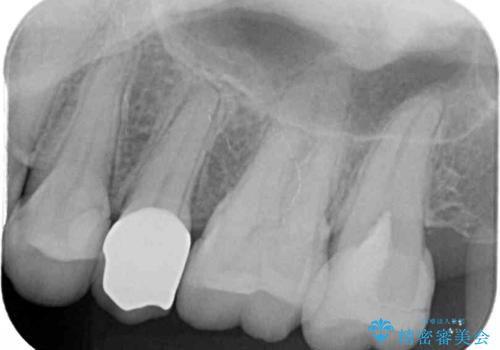

診査をしたところ、レントゲン写真よりとても大きなむし歯があることが分かりました。

虫歯が歯髄腔(神経の部屋)に達している可能性が非常に高かったため、炎症を起こしている神経組織を部分的に切除し、歯根部分の神経組織を保存する治療法が望ましいと考えられました。

虫歯は深くまで進行しており、歯冠部の神経から出血が認められました。神経を部分的に除去したところ出血が治まったので、生体親和性の非常に高いセメントにて充填し、仮封をしました。

欠損歯質は比較的小さかったため、セラミックインレーにて修復治療を行いました。